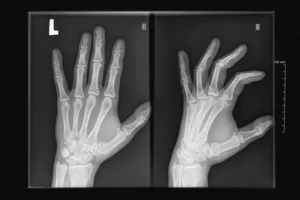

손가락 변형

손가락 변형의 종류는 백조목은 마치 백조의 목처럼 손가락의 중간 마디가 펴지고, 끝 마디가 구부러지는 변형입니다. 부토니에르 변형, 만곡수지 방치하면 손가락이 굽거나 휘어지는 변형이 나타날 수 있습니다.